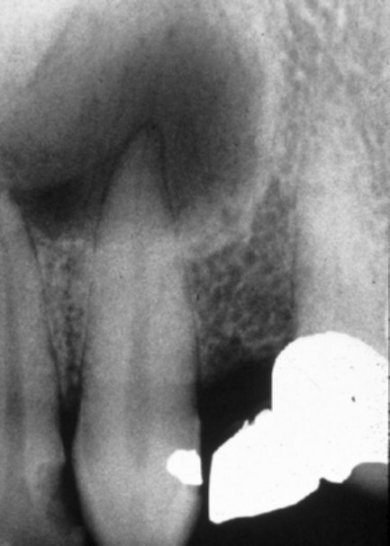

- Εχει παρόμοια ακτινογραφική εικόνα με το ακρορριζικό κοκκίωμα: σαφώς περιγεγραμμένη διαύγαση που περιβάλλεται συνήθως από ακτινοσκιερή γραμμή.

- Οι εκτεταμένες ακρορριζικές κύστεις προκαλούν έκπτυξη, λέπτυνση και πιθανόν και λύση των συμπαγών πετάλων.

- Το ακρορριζικό τμήμα του δοντιού εισέρχεται στη διαύγαση και συνήθως παρατηρείται απώλεια της lamina dura του υπεύθυνου δοντιού

- Είναι δυνατόν να παρεκτοπίζει τις ρίζες των παρακειμένων δοντιών αλλά σπανίως προκαλεί απορρόφηση αυτών.